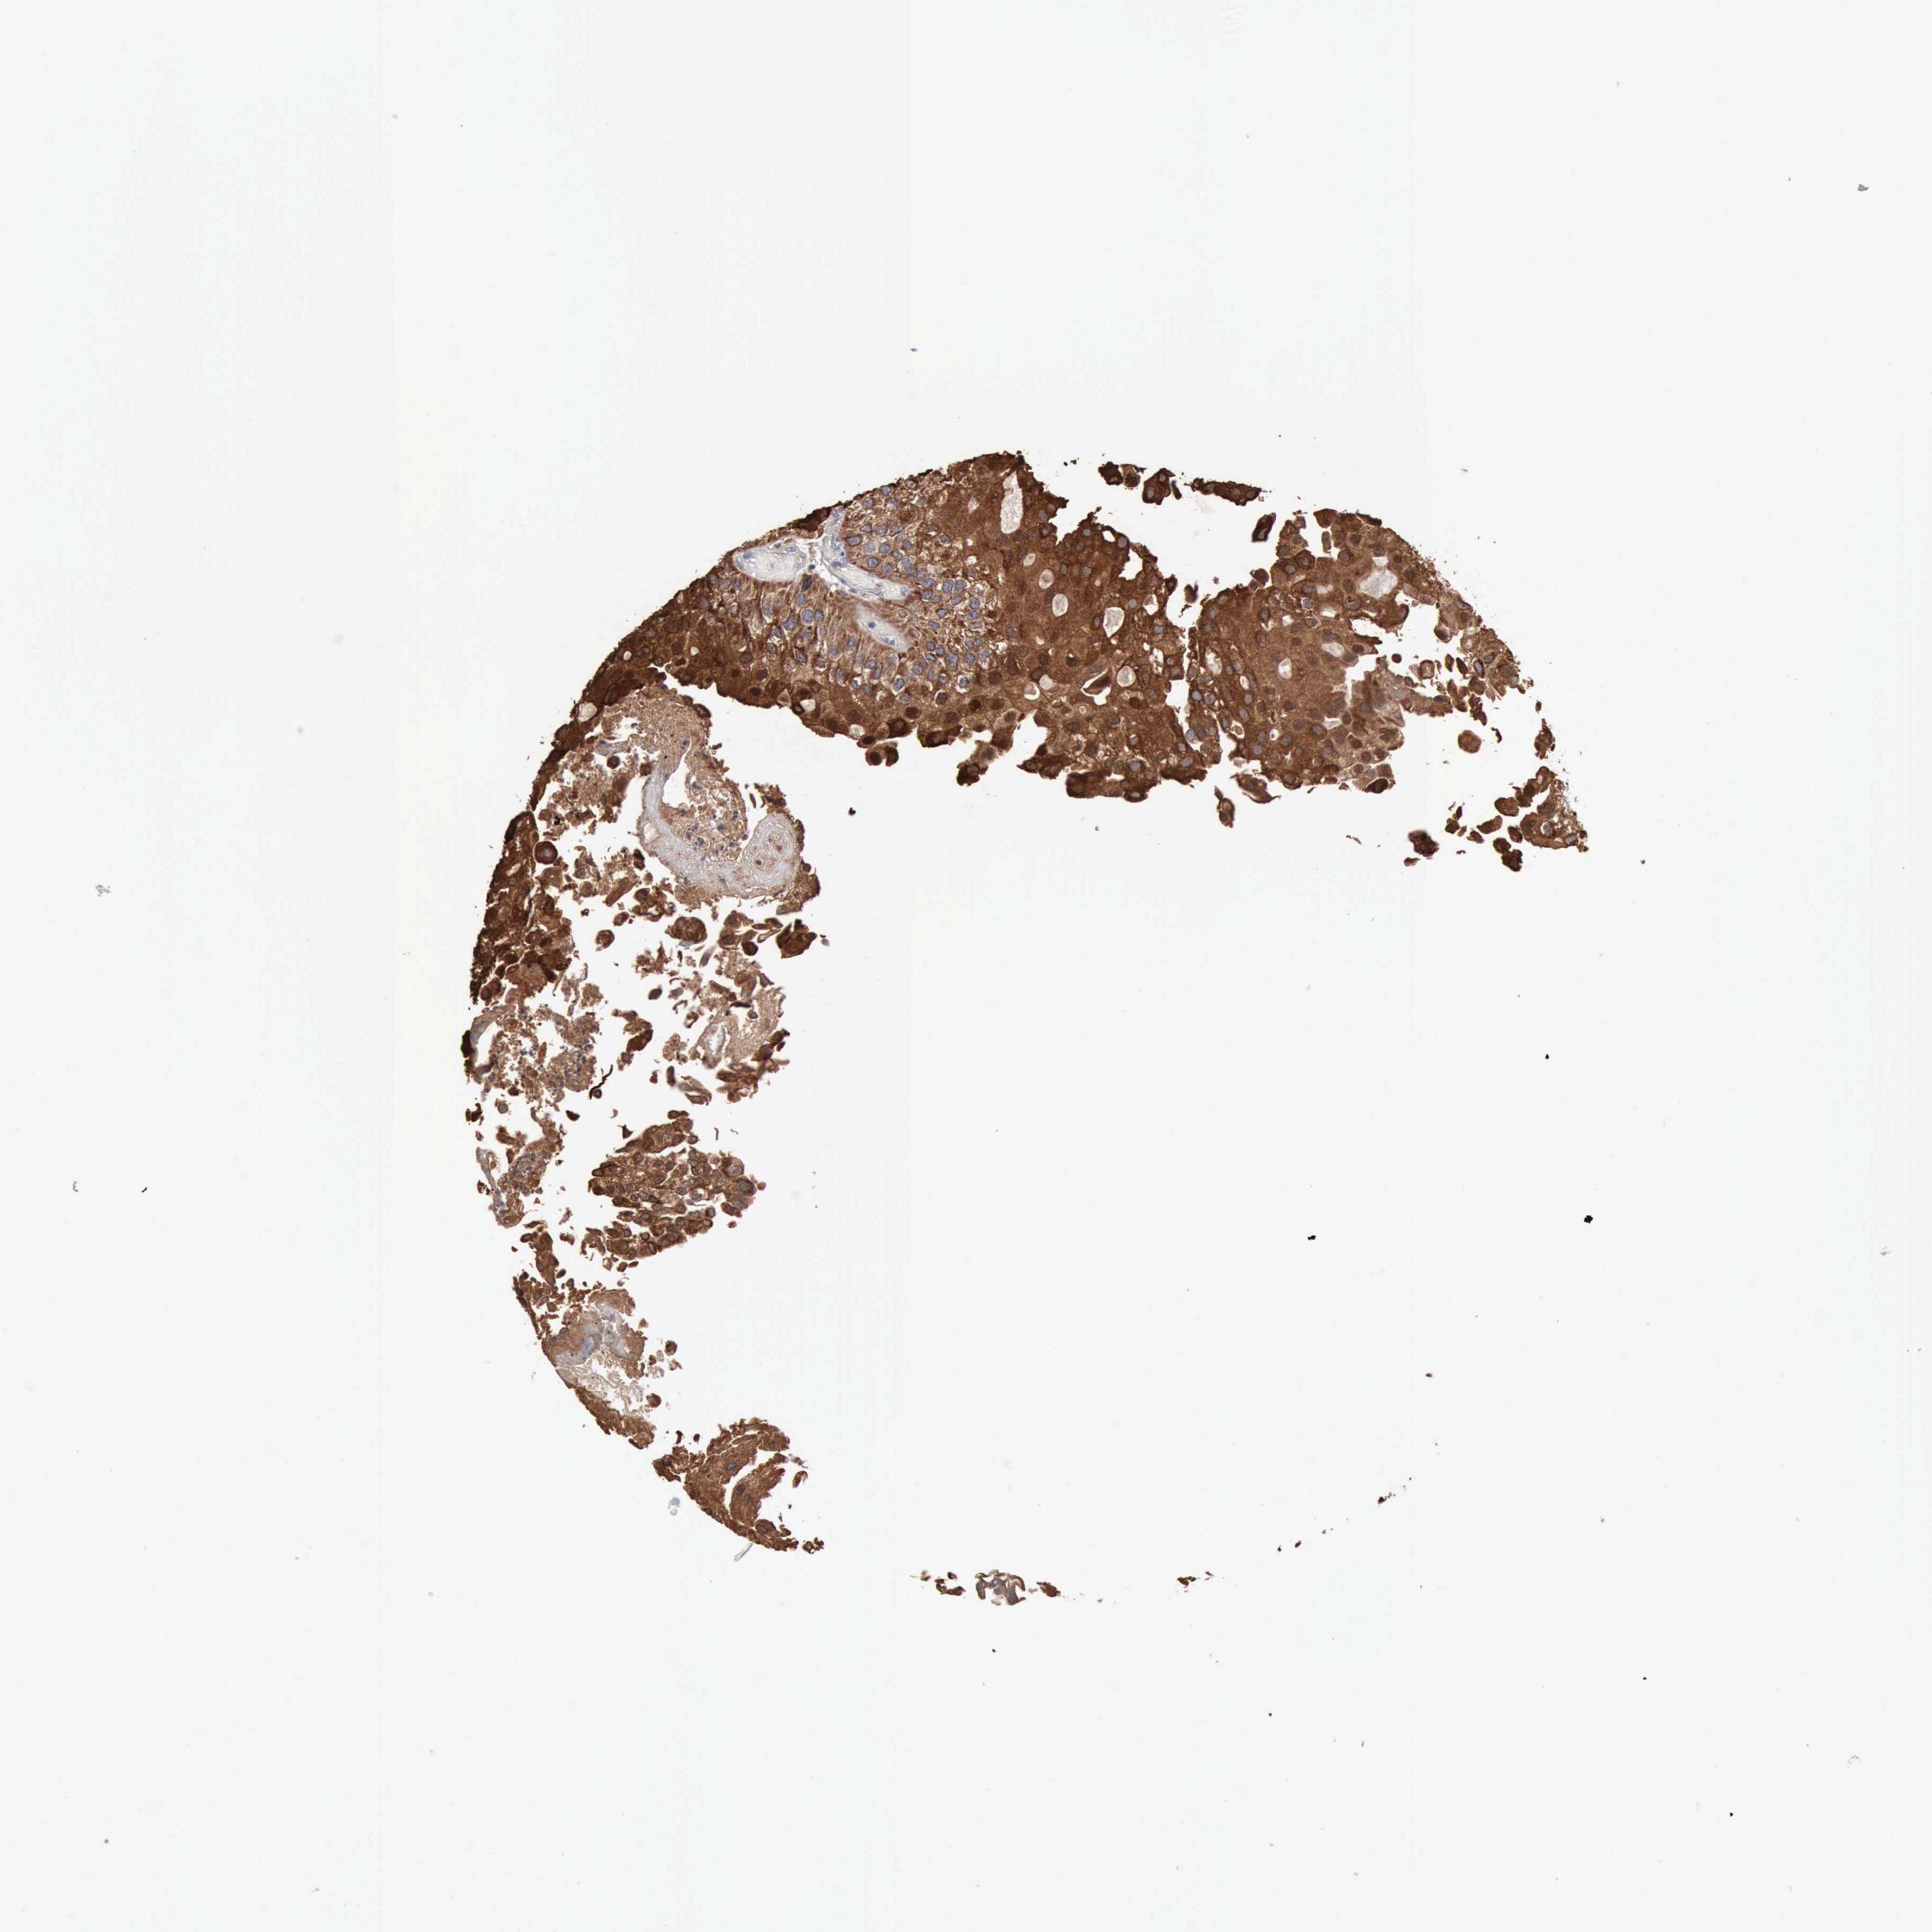

UROTHELIAL CANCER - Protein expressioni

A mouse-over function shows sample information and annotation data. Click on an image to view it in a full screen mode. Samples can be filtered based on level of antibody staining by selecting one or several of the following categories: high, medium, low and not detected. The assay and annotation is described here.

Note that samples used for immunohistochemistry by the Human Protein Atlas do not correspond to samples in the TCGA dataset.

Antibody stainingi

Antibody staining in the annotated cell types in the current human tissue is reported as not detected, low, medium, or high, based on conventional immunohistochemistry profiling in selected tissues. This score is based on the combination of the staining intensity and fraction of stained cells.

Each image is clickable and will lead to virtual microscopy that enables deeper exploration of all samples and also displays staining intensity scores, fraction scores and subcellular localization as well as patient and tissue information for each sample.

Antibody HPA001078

Antibody CAB026695

Staining

High

Medium

Low

Not detected

Intensity

Strong

Moderate

Weak

Negative

Quantity

>75%

75%-25%

<25%

None

Location

Nuclear

Cytoplasmic/membranous

Cytoplasmic/membranous,nuclear

Urothelial carcinoma, High grade